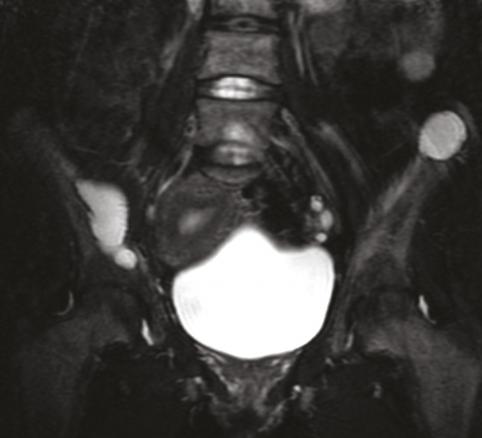

Cette femme de 31 ans sans antécédents était adressée pour des douleurs pelviennes, un syndrome polyuro-polydipsique et une altération de l’état général. Le bilan biologique montrait une hypercalcémie, une hypophosphorémie, une hypovitaminose D et une hyperparathormonémie. La tomodensitométrie (TDM) [fig. 1 ] et l’imagerie par résonance magnétique (IRM) [fig. 2 ] du pelvis révélaient un aspect ostéolytique diffus avec des nodules tumoraux des ailes iliaques. La scintigraphie et l’examen histologique de trois volumineuses glandes parathyroïdes permettait de retenir le diagnostic d’hyperplasie parathyroïdienne primaire. La biopsie osseuse confirmait le diagnostic de tumeurs brunes osseuses associées à l’hyperparathyroïdie. L’évolution était favorable sous traitement symptomatique et antalgique.